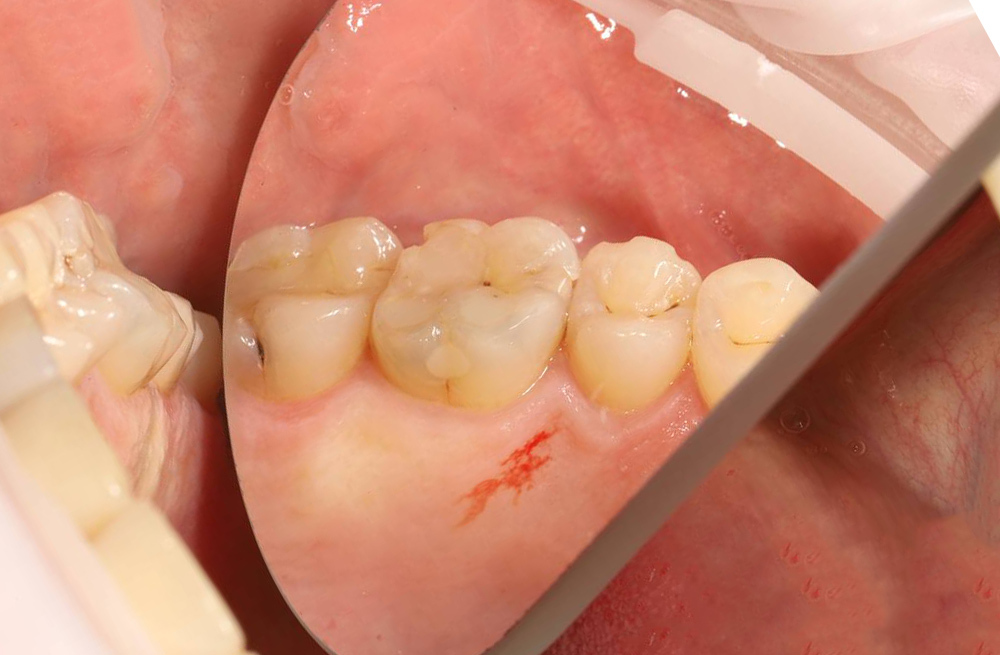

Устранение кариеса на боковом пункте моляра с послойным моделированием и полировкой пломбы